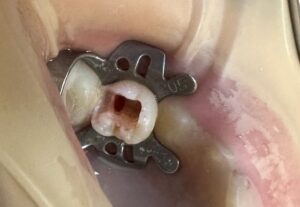

麻酔注射 して

ラバーダム防湿 して

【生活歯髄切断法】 にて 根管歯髄は 活かして

保存治療。

人生 初 の ラバーダム防湿

興味津々 で 受けて いました。